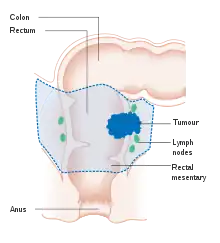

Location and appearance of two example colorectal tumors

Colon cancer with extensive metastases to the liver